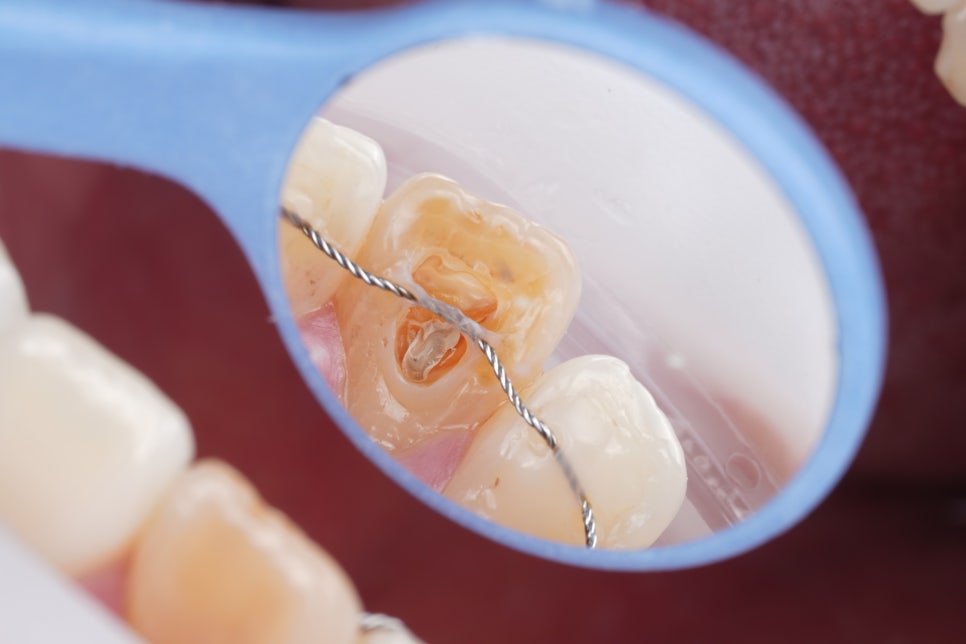

실활치 미백을 진행했어요.

촬영일 : 250905

아주 오래 전에 타치과에서

신경치료를 실패한

경험이 있으셨습니다.

오래된 약재를 제거하고

깨끗하게 비운 신경관을 밀폐한 후

치아 내부에 미백 약제를 넣었어요.

변색 원인이 된 내부 성분을 분해하고

점차 밝은색으로 회복되도록 유도했어요.

마치 치아 속에 꺼져 있던 조명을

하나 켜주는 과정이라고

보시면 이해하기 쉬워요.